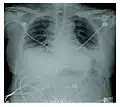

Rapid progression from initial symptoms to respiratory failure is a key feature. An X-ray that shows ARDS is necessary for diagnosis (fluid in the small air sacs (alveoli) in both lungs). In addition, a biopsy of the lung that shows organizing diffuse alveolar damage is required for diagnosis. This type of alveolar damage can be attributed to nonconcentrated and nonlocalized alveoli damage, marked alveolar septal edema with inflammatory cell infiltration, fibroblast proliferation, occasional hyaline membranes, and thickening of the alveolar walls. The septa are lined with atypical, hyperplastic type II pneumocytes, thus leading to the collapse of airspaces. Other diagnostic tests are useful in excluding other similar conditions, but history, X-ray, and biopsy are essential. These other tests may include basic blood work, blood cultures, and bronchoalveolar lavage.